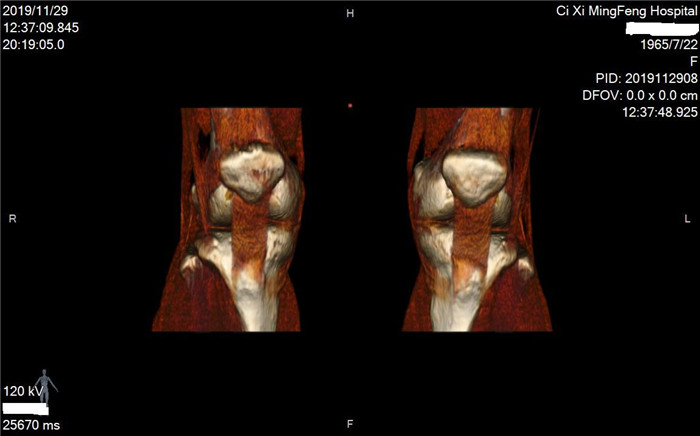

明峰CT搭載了領先的硬件技術平臺及系統,強大的掃描能力可滿足臨床的各種要求,呈現更極致的細節,為各臨床科室提供高品質的圖像。薄層掃描,消除部分容積效應,提高各向同性。配合高分辨率算法,有助于細微結構和形態學顯示。